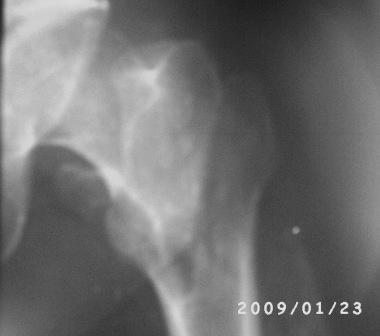

Больному 50л. В отдаленном от центра р-не ДТП 6.12.08г. д-з " тяжелая ЧМТ, мн.перломы ребер слева,отрыв ножки селезенки, повреждение п/ж железы, з/двойной перелом прав.бедра.

После экстрен. хирургических вмешательств, конечность фиксирована кокситной гипсовой лонгетной повязкой. Кома 2 нед, нагноение п/о раны живота, посттравмат. пневмония. 20.01.09г. переведен к нам. Постельный больной, ослабленный,бледный, весом 56кг: свищ п/о раны перед. брюшной стенки с сукровичным выделением, гипс снят - деформация и укорочение бедра на 6 см, в обл перелома есть спайка. слабо, но активно поднимает ногу, контрактура т/б и коленных суставов. Обшеукреп. лечение, компоненты крови, общ. массаж, ЛФК и больной активизирован, начал ходить с костылями, движения в суставах почти восстановлены. НВ-112, эр-3,5млн. Наш план блокир. и/м остеосинтез. Имеется гвозди для ВНПБ ЦИТО, но PFN не имеется

Вертельный перелом уже срастается в приемлемом положении отломков. Для сохранения шеечно-диафизарного угла в проксимальной опоре аппарата по оси шейки можно ввести 2-3 стержня.